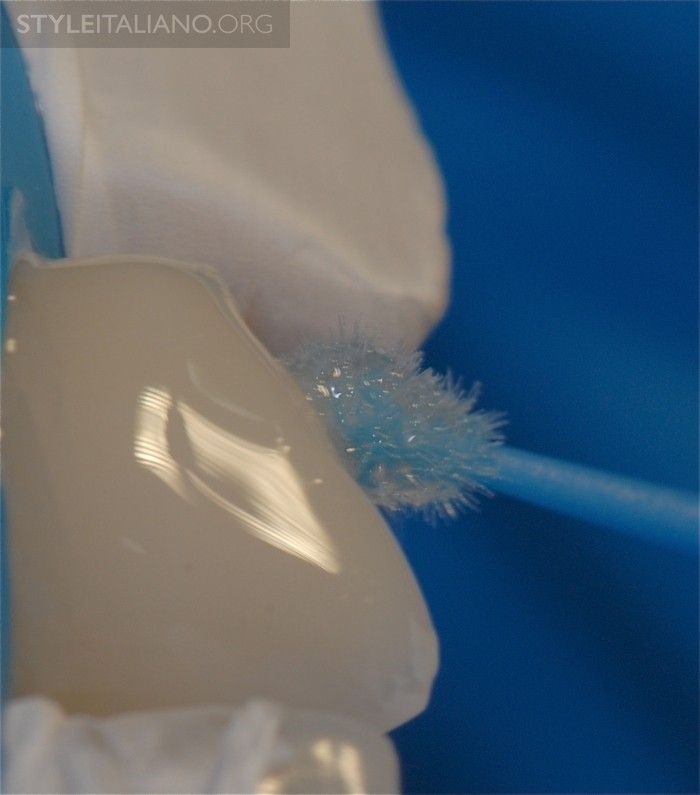

Hình 6. Đài cao su đánh bóng sứ được sử dụng để làm nhẵn lại đường viền.